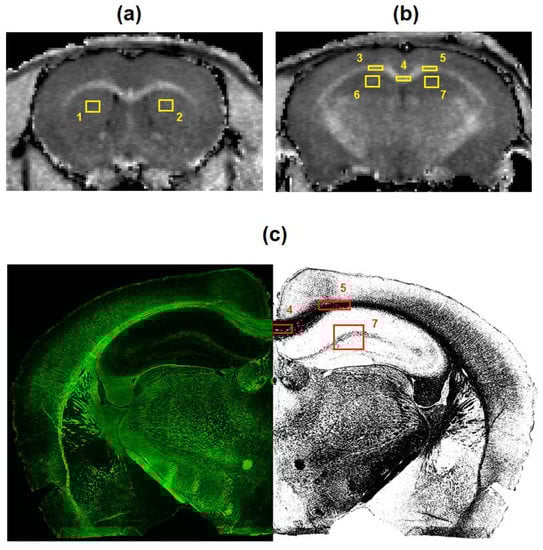

2.4. Image Analysis